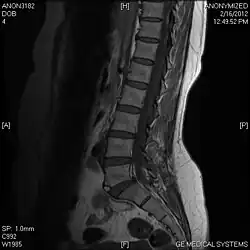

T2 W Sagittal image

Limbus Vertebra L5